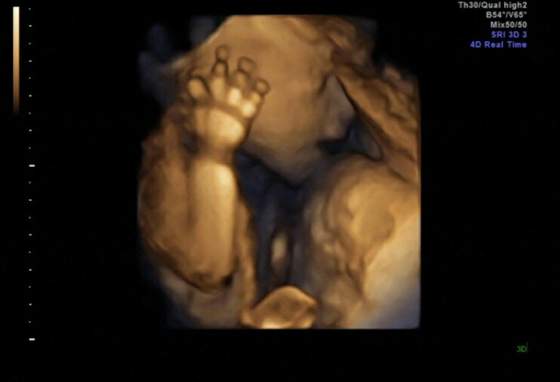

Jaki ladnyw dzidzius Kropku

Kropek ale śliczne fotki! Takie super wyraźne. Cudna pamiątka :-)

kropekk na kopie juz widze

super i jak buzke otworzyl/a ja nie moge ale to fajne tez chce juz